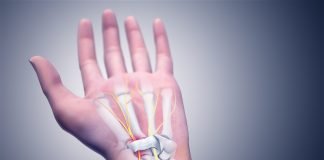

Sindromul de canal carpian – Simptome, cauze si tratament

Sindromul de canal carpian este o afectiune medicala ce se caracterizeaza prin leziuni dureroase si invalidante ale degetelor, ale articulatiei pumnului, ale cotului si...